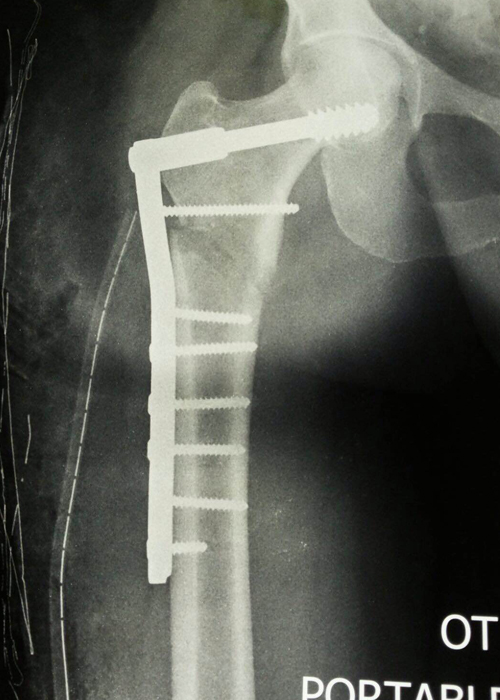

Case:1 Polytrauma Case (Multiple Fractures in Ipsilateral Limb)

Pre-Op Hip (AP & Lateral)

Post-Op Hip